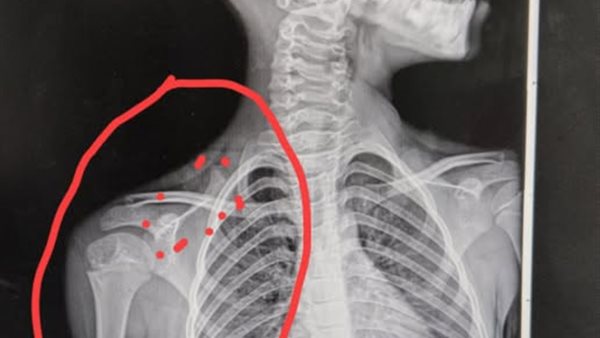

ومع استمرار الألم وتكوّن ورم واضح أسفل الرقبة، قررت أسماء مراجعة طبيب ثالث، والذي لم يقدّم تفسيرًا مختلفًا، مما دفع نجلها الأكبر إلى إرسال صورة الأشعة لـ ChatGPT عبر الإنترنت.

المفاجأة، كما تروي الأم، أن ChatGPT حلل الأشعة وحدّد موضع الإصابة بدقة، وأشار إلى وجود خلع في عظمة معينة، ليتضح لاحقًا أن هذا التشخيص أقرب إلى الحقيقة من تقديرات الأطباء، كما قدّم البرنامج خطة مبدئية للتعامل مع الحالة، محذرًا من احتمالية الحاجة إلى تدخل جراحي، وهو ما أكدته التطورات لاحقًا.

وقالت أسماء في منشور على وسائل التواصل: الدكاترة صفر، وشات جي بي تي عشرة، هو اللي شخّص الحالة وقال اسم العظمة اللي اتخلعت، وفعلًا هو نفس المكان اللي ورم، ومشينا على كلامه وبدأت الحالة تتحسن